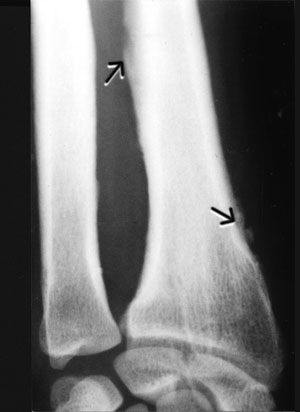

A chest x-ray was normal, but x-ray of the wrist showed periosteal elevation and periosteal reaction at the distal end of the radius (Box, Figure B).